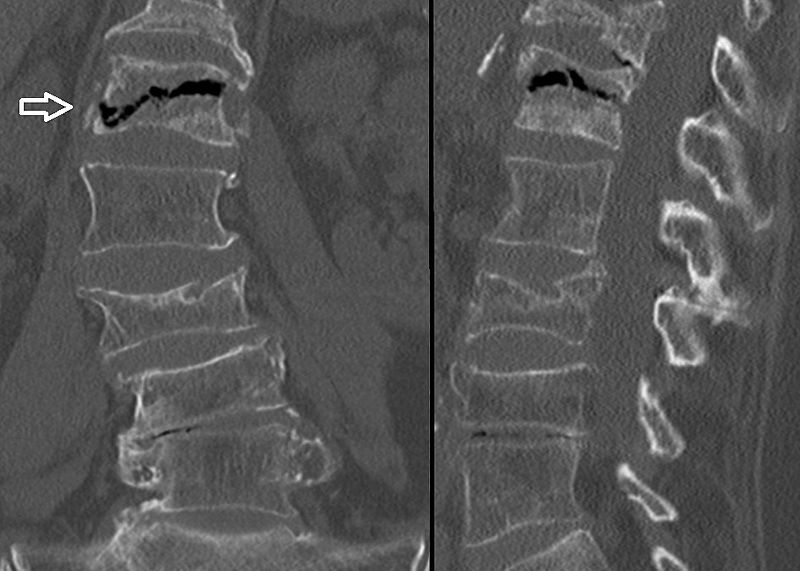

The main differential to osteoid osteoma is an osteoblastoma.

Osteoblastomas are similar to osteoid osteomas, however osteoblastomas are larger bigger (> 2.0 cm), may develop in the vertebrae, and manifests as bone pain that is not relieved by aspirin.